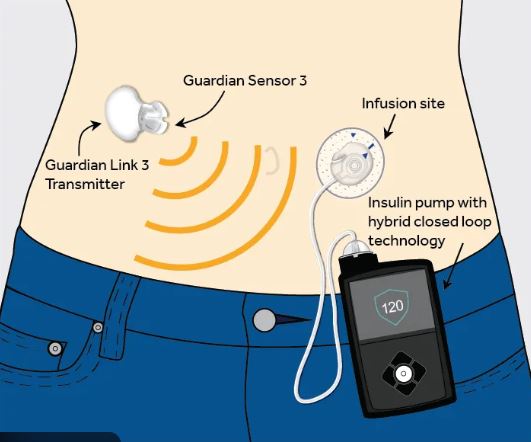

5. Oral Bacteria & Diabetes

This is a vicious cycle:

Gum disease → diabetes

- Chronic gum inflammation makes insulin resistance worse.

- Certain bacteria increase inflammatory cytokines that raise blood sugar.

- People with severe gum disease have higher HbA1c levels.

Diabetes → gum disease

- High blood sugar feeds bacteria.

- Poor healing leads to deeper gum pockets.

- More gum pockets → more bacteria → more inflammation.

Both conditions worsen each other.